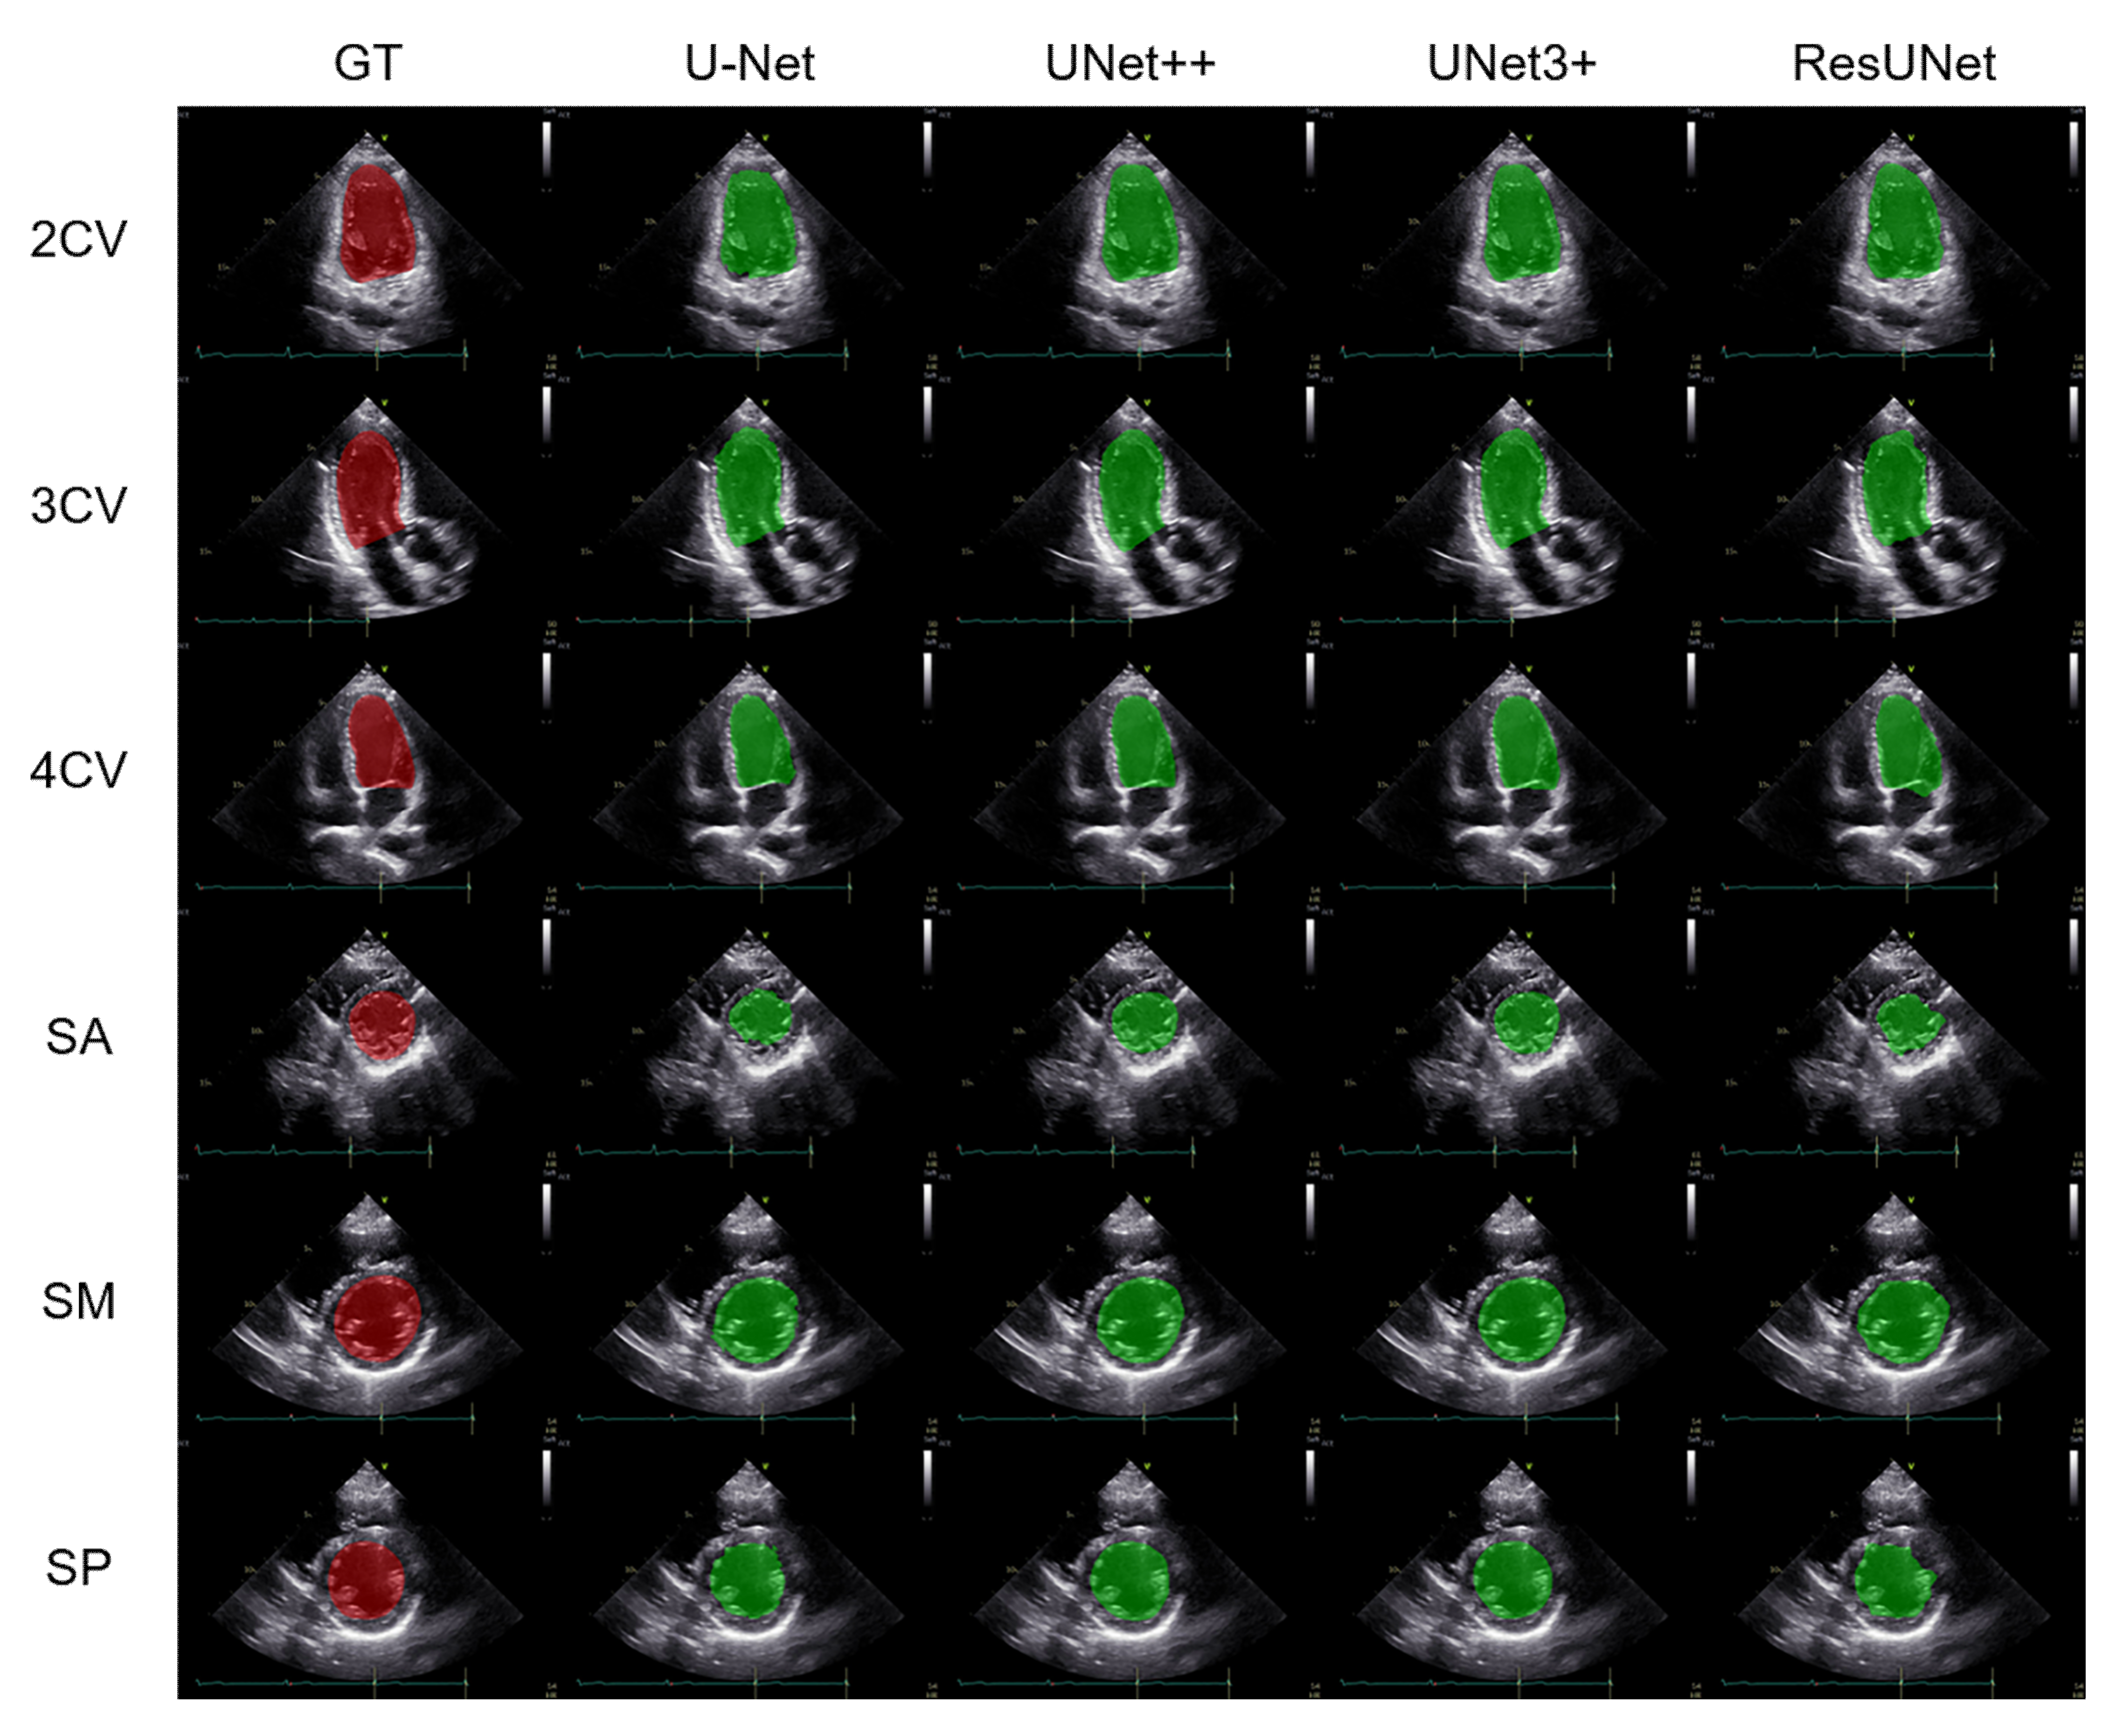

3.1. Performance Comparison of the Segmentation Methods